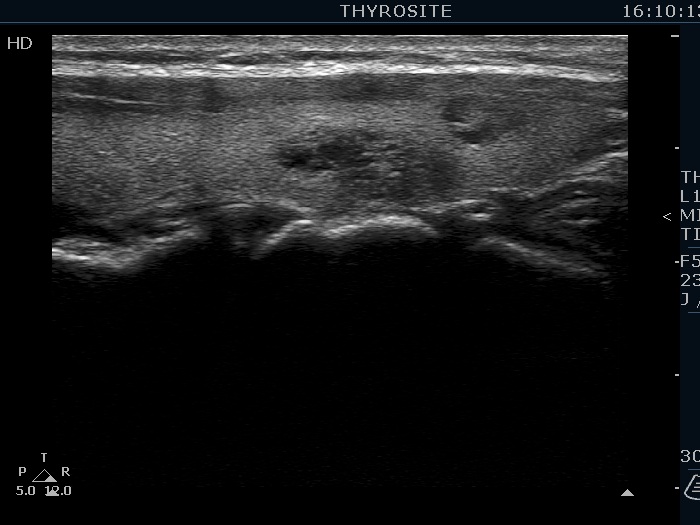

Ultrasonography. The thyroid was echonormal. There were several hypoechoic nodules in the left lobe. The middle one had back wall cystic figures. There were 3 or four discrete, deeply hypoechoic lesions above and lateral to the left lobe in the neck. One of them presented with a hilum-like figure while the others lacked hilum.

The lymph nodes had a non-typical presentation. They lacked a regular hilum.